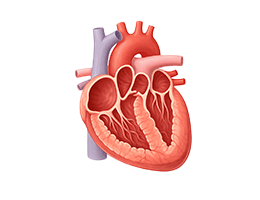

심근경색 (Myocardial Infarction)

협심증 (Angina Pectoris)

부정맥 (Arrhythmia)

심근병증 (Cardiomyopathy)

심장판막질환 (Valvular Heart Disease)

심부전 (Heart Failure)